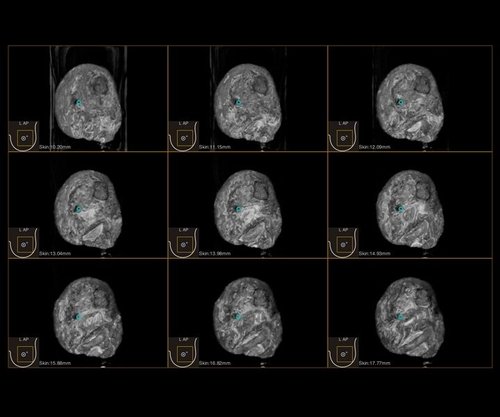

Das IBUS 60 ist ein intelligentes Brust-Vollvolumen-Ultraschallsystem der Marke SIUI.

Das IBUS 60 zeichnet sich durch Sicherheit und Komfort aus. Es bietet ein hochauflösendes Bild und reduziert somit Fehldiagnosen, was ideal für die Brustuntersuchung ist, insbesondere bei einer dichten Brust.

• Dreidimensionale Positionierung